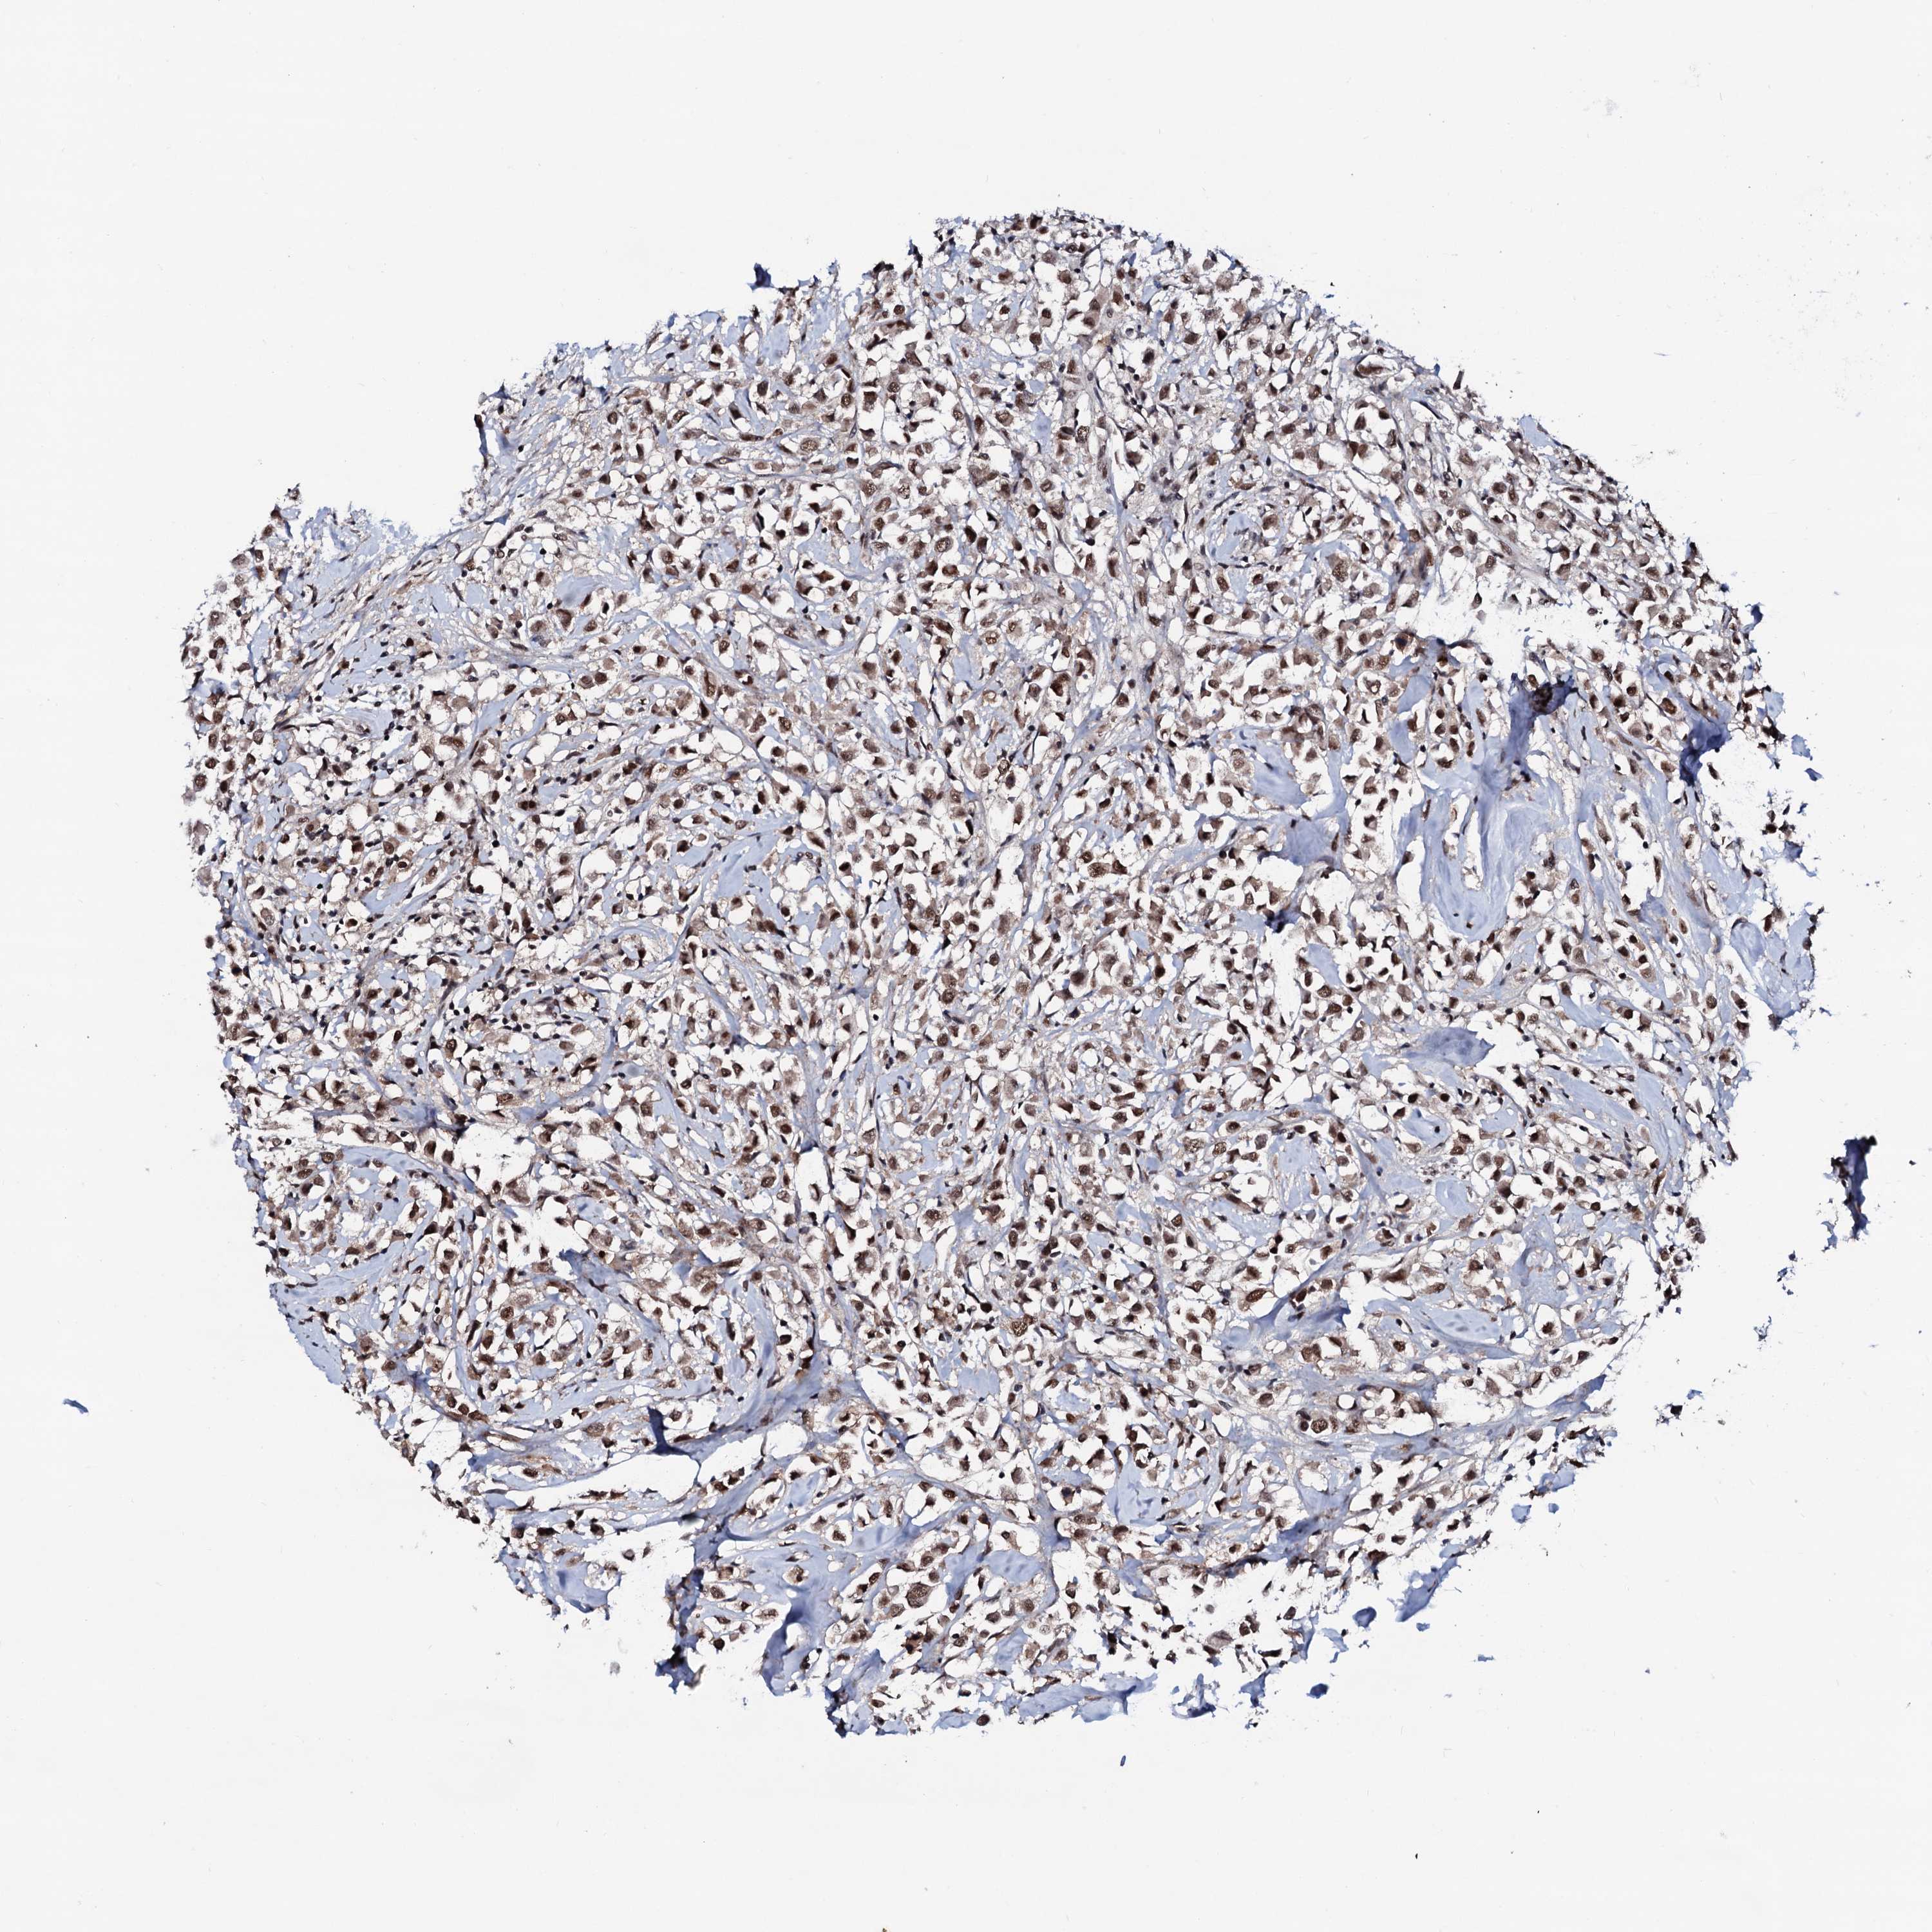

CANCER BREAST CANCER Show tissue menu

BRCA TCGA BRCA VALIDATION PROTEIN EXPRESSION

Breast cancer

Human cancer

Breast invasive carcinoma

PRPF18 is not prognostic in Breast Invasive Carcinoma (TCGA)